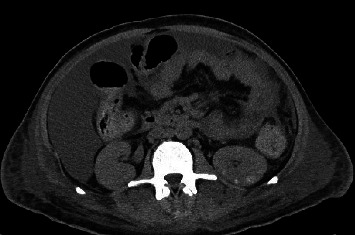

Abstract Image

Kaposi sarcoma (KS), an angioproliferative neoplasm driven by human herpesvirus 8, predominantly affects patients with acquired immune deficiency syndrome (AIDS) or those on immunosuppressive therapy. Gastrointestinal involvement in KS is underreported, with limited literature highlighting its clinical significance and morphological diversity on endoscopy. This case report illustrates the complexities of diagnosing and managing gastrointestinal KS in an AIDS patient who presented with upper gastrointestinal bleeding. The diagnosis was established through the characteristic endoscopic appearance of the lesions, supported by histopathological confirmation. This case emphasizes the variable endoscopic manifestations of KS, ranging from linear ulcers to nodular lesions, and underscores the necessity for heightened clinical vigilance and multiple deep biopsies to avoid false-negative results. Treatment options, primarily palliative, include highly active antiretroviral therapy, chemotherapy, and radiation, yet the prognosis remains poor with high short-term mortality. This report contributes to the sparse literature on gastrointestinal KS, advocating for increased awareness and early intervention to potentially improve outcomes in this patient population.